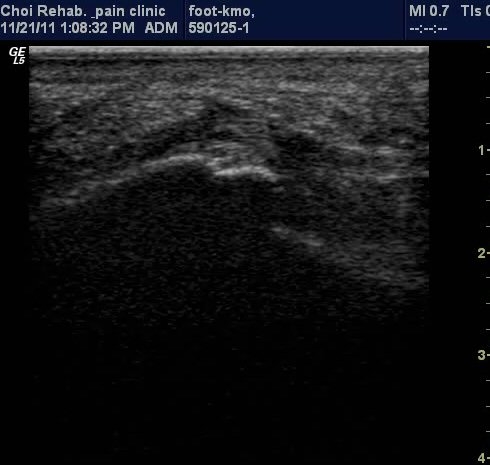

Ⱦ´Ü¸é°Ë»ç¿¡¼­µµ Á·Àú±Ù¸·ÀÇ Àú¿¡ÄÚ ºÎÁ¾ÀÌ ¶Ñ·ÈÇÔ(±×¸² 3).